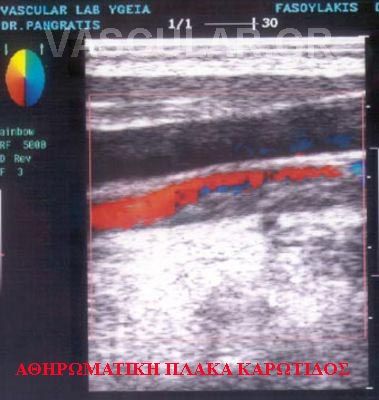

Ç Duplex åîÝôáóç óõíäõÜæåé ôçí high resolution imaging ç ïðïßá åîáóöáëßæåé ôçí ãñÞãïñç åîÝôáóç ôçò áíáôïìßáò ôïõ áããåßïõ , ôçí áðïêÜëõøç êáé åêôßìçóç ôùí áèçñùìáôéêþí áëëïéþóåùí üðùò åðßóçò êáé ôçí áðåéêüíéóç ôçò õöÞò êáé ôçò óõíèÝóåùò ôçò áèçñùìáôéêÞò ðëÜêáò. Åíþ ç öáóìáôéêÞ áíÜëõóéò åîáóöáëßæåé ôïí êáèïñéóìü ôùí äéáôáñá÷þí êáé ôùí ÷áñáêôçñéóôéêþí ôçò áéìáôéêÞò ñïÞò, âïçèþíôáò åéò ôçí áíáãíþñéóç ôïõ áããåßïõ óôçí åíôüðéóç ôùí áéìïäõíáìéêþí äéáôáñá÷þí, êáé ôçò ôá÷ýôçôïò êáé ôïí åðáêñéâÞ êáèïñéóìü ôçò èÝóåùò êáé ôïõ âáèìïý ôçò óôåíþóåùò ðïóïôéêÜ êáé ðïéïôéêÜ.

Åäþ èá Þèåëá íá áíáöåñèþ óå ìéá ó÷åôéêÜ, íÝá åìðåéñßá åéò ôçí áããåéïëïãßá ç ïðïßá áíáöÝñåôáé ùò intimal disease/åíäïèçëéáêÞ íïóïò Intimal Thickening êïéíÞò êáñùôßäïò äçëáäÞ ôçí ðÜ÷õíóç ôïõ Ýóù ÷éôþíïò, ôïõ åíäïèçëßïõ, ðïõ äåí áðïêáëýðôåôáé ìå êáììéÜ Üëëç ìÝèïäï óõìðåñéëáìâáíïìÝíçò êáé ôçò áããåéïãñáößáò. Ç åîáêñßâùóç ôçò ðñùßìçò áèçñùìáôéêÞò íüóïõ åßíáé ç âáóéêÞ ìåëÝôç ãéá ôçí ðáñáêïëïýèçóç ôçò åîåëßîåùò êáé ôçò ìåëëïíôéêÞò áíáðôýîåùò ôçò áèçñùìáôéêÞò íüóïõ ãéá ôçí Ýãêáéñï êáé óùóôÞ áíôéìåôþðéóç.

Ïóïí áöïñÜ ôçí ìïñöïëïãßá ôçò ðëÜêáò èá Þèåëá íá áíáöåñèþ ìüíï óôï üôé ìå ôçí áíÜëõóç ôçò åéêüíïò, åîáóöáëßæåôáé ìßá ëåðôïìåñÞò åéêüíá ôçò õöÞò êáé ôçò óõíèÝóåùò ôçò áèçñùìáôéêÞò áëëïéþóåùò, ç ïðïßá óõíÞèùò áðïôåëåßôáé áðü õðåñç÷ïãåíÞ åíáðüèåóç áóâåóôßïõ åíþ óå Üëëåò ðåñéðôþóåéò Ý÷ïõìå ìáëáêÜ ç÷ïãåíÞ óôïé÷åßá ãéá ðñüóöáôåò áëëïéþóåéò Þ êáé áíç÷ïãåíåßò ðåñéï÷Ýò.(4)

Ç õøçëÞ áíÜëõóç ìå 10 MgHz ôçò åéêüíïò ìáò äßäåé ôçí äõíáôüôçôá íá áðïêáëýøïõìå ôçí êáëÞ êáôÜóôáóç Þ ü÷é ôçò åóùôåñéêÞò åðéöáíåßáò ôçò áèçñùìáôéêÞò ðëÜêáò ìå ôçí åíôüðéóç ìéáò åîåëêþóåùò åðß ôçò áëëïéþóåùò åíôüò ôïõ áõëïý ìå ôéò ãíùóôÝò åðéðôþóåéò üðùò åßíáé ç äçìéïõñãßá ìéêñþí åìâüëùí üðùò áêüìç êáé ìå ôçí åíôüðéóç ôçò áéìïññáãßáò áðü ôçí åîåëêùìÝíç ðëÜêá ôçí ãíùóôÞ Intraplaque Hemorrhage ç ïðïßá óõíÞèùò áíåõñßóêåôáé ìå åôåñïãåíåßò áëëïéþóåéò .